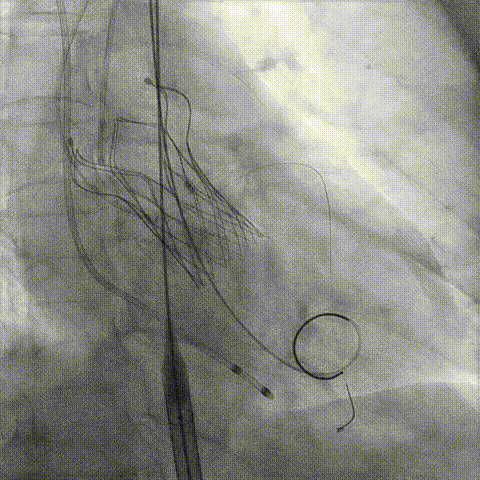

第一次释放

再次评估左冠开口,考虑调整瓣膜深度

回收后调整深度,再次释放

评估左冠开口

左冠开口切线位造影

决定左冠烟囱支架保护冠脉

调整支架位置